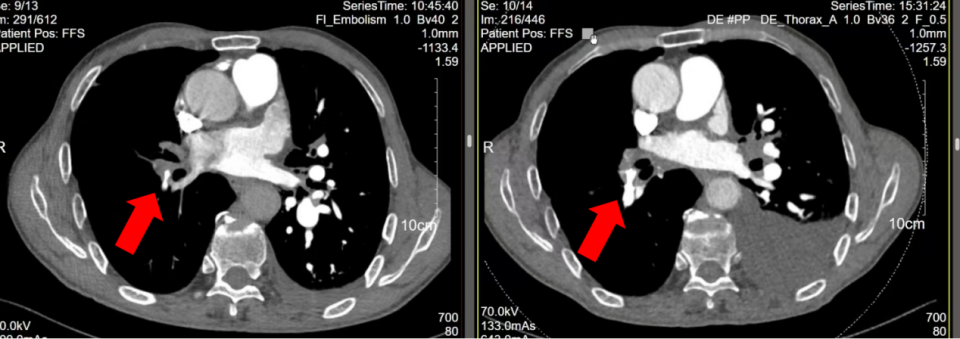

通过左房CTA,我们的确发现患者的两个肺血管异常:1、左上肺静脉、右肺静脉中支未显影,提示存在局部静脉闭塞或缺如(图3a箭头所示);2、左下肺动脉多个分支扩张(图3b箭头所示)。

图片

图3a:左房CTA提示左上肺静脉未显影

图3b:左房CTA提示左下肺动脉分支扩张